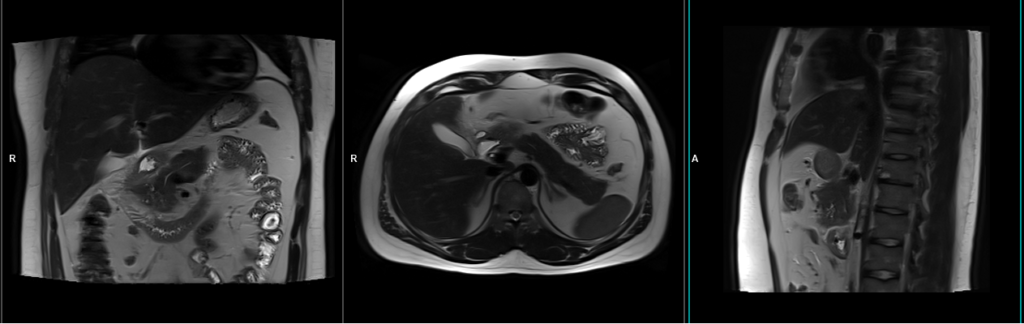

MRI Pancreas Localiser

To localize and plan the sequences, it is essential to acquire a three-plane T2 HASTE localizer initially. These fast single-shot localizers have an acquisition time of under 25 seconds and are highly effective in accurately localizing abdominal structures.